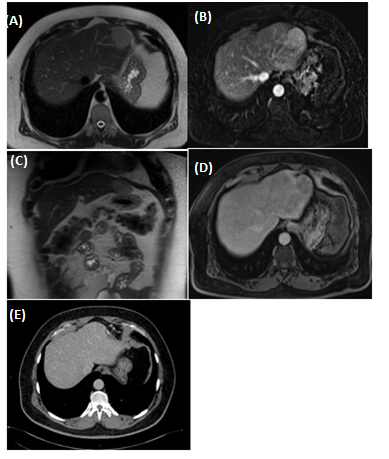

Male, 47years old with an incidental finding of hepatic lesion, during investigation of nephrolithiasis. Previous history of splenectomy after abdominal trauma due to automobile accident 20years ago. Hypertensive in use Olmesartan. Denied other pathologies and surgeries. On physical examination: good general condition, anicteric, painless abdomen, without palpable masses. Laboratory tests: Hb 14g/dL (13,5- 17,5), Hct 44,4% (39-55), Platelets 268,000/mm3 (150.000 - 400.000), creatine 0,9mg/dL (1,5), INR 0,8, CEA 1,33ng/mL (<3,0), CA 19-9 20U/mL (<37), AFP 1,5ng/dl (<7,22 ), albumin 4,19g/dL (3,4- 4,8), AST 20U/L (17-55), ALT 18U/L (21-71), GGT 54U/L (15/73), AP 48U/L (38-126), total bilirrubin 0,57mg/dL (0,2-1,3). MRI showed nodular hepatic lesion, 42x41x28mm, slight hyperintense in T2, with contrast enhancement and washout in late phase, in segment II, without dilatation of biliary tract (Figures 1). The initial diagnosis was hepatic adenoma. Proceeded with hepatic segmentectomy, with good evolution. The surgical specimen referred to pathological anatomy and revealed hepatic splenosis (Figures 2 & 3).

Figure 1 Magnetic Resonance Imaging (MRI).

T2-weighted (A & B) and T1-post-contrast (C, D and E) images, in axial (A, C, D and E) and coronal (B) planes, that demonstrate subcapsular nodule in liver segment II, with intermediate sign in T2, enhancement in the post-contrast arterial phase (C) and washout with capsular enhancement in the venous phase (D). Signs of splenectomy and small implants of splenic tissue in the left subphrenic region (E) are also noted.

Intrahepatic splenosis shows increased enhancement on CT or MR images during the arterial phase. Performing gadoxetic acid–enhanced hepatocyte-phase MR imaging does not help because intrahepatic splenosis is hypointense during the hepatospecific phase. The MR technique involving administration of small iron oxide particles (SPIO-Endorem), which is taken up by liver and spleen reticuloendothelial cells, has proven to be effective in differentiating intra-hepatic splenosis from other lesions.13,14,17 With SPIO (superparamagnetic iron oxide) intrahepatic splenic nodes remain hyperintense.18 Noncontrast CT reveals a well circumscribed iso- or hypodense mass in the liver, while noncontrast MRI demonstrates mild-to-moderate hyperintensity on T2-weighted image and hypointensity on the T1-weighted image. A dynamic study on CT and MRI shows a slight to intense enhancement, which may be homogeneous or heterogeneous during the arterial phase but enhancement is diversely during the portal venous and equilibrium phases in different cases. Compared with the surrounding hepatic parenchyma, the lesion could reveal hypodensity and hypointensity, or hyperdensity in the arterial phase. Or it can demonstrate diminished enhancement, slight enhancement, or increased enhancement during the following phases (Figures 1 & 2).18,19